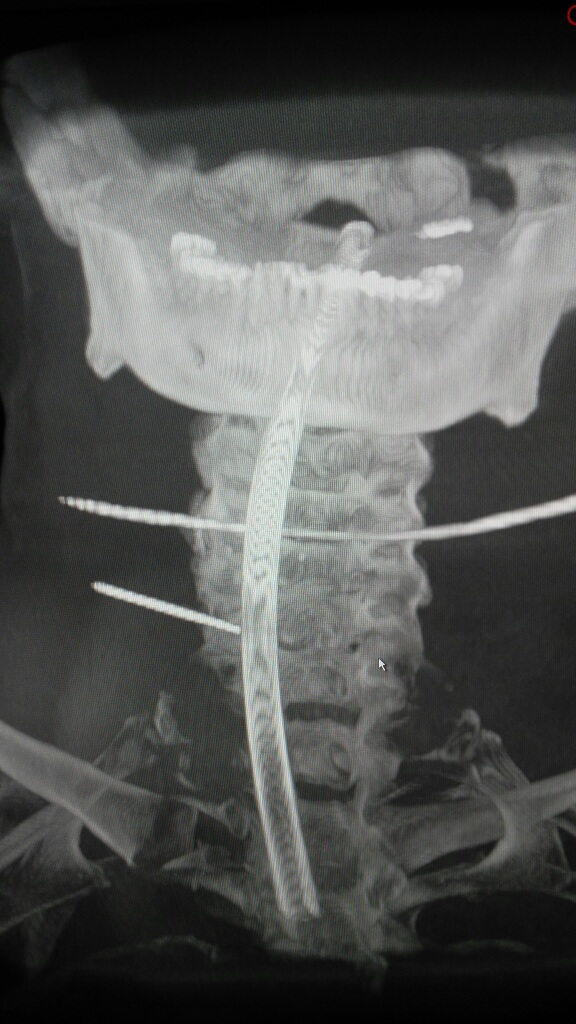

术中O-ARM确定人工椎间盘位置好

手术顺利,手术时间2小时,出血30毫升,术后患者双上肢麻木好转。